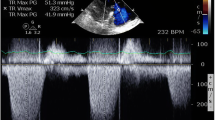

Current guidelines recommend transthoracic echocardiography (TTE) as the first-line, noninvasive imaging investigation when suspecting PH [1]. Indeed, regardless of the underlying cause, PH leads to echocardiography-detectable right ventricle (RV) pressure overload and dysfunction. Notably, echocardiography allows defining the probability of PH (low, intermediate, or high), thus prompting further investigation, including cardiac catheterization. Furthermore, TTE provides a reproducible assessment of potential left heart causes of PH, including valvular disease, left ventricle (LV) systolic or diastolic dysfunction, congenital heart disease (CHD), and intra-cardiac shunts [10]. Besides conventional TTE, speckle-tracking strain imaging and 3D echocardiography are gaining ground in monitoring right heart structure and function [11]. The assessment of RV systolic pressure is obtained with the tricuspid regurgitation jet velocity and size/collapsibility of the inferior vena cava [12]. In selected patients, transesophageal echocardiography (TEE) may further ambiguous findings, e.g., mitral valve disease, ultimately refining the patient treatment [10].